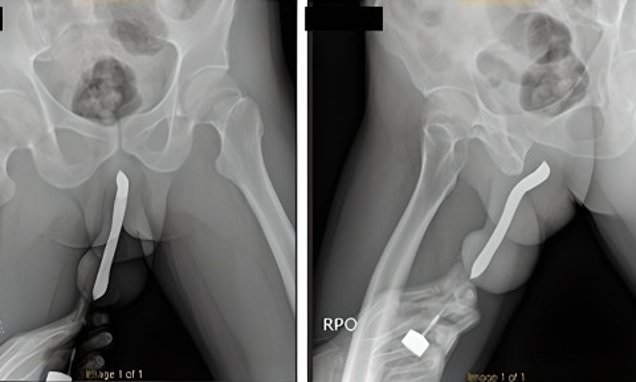

A man was left in excruciating pain after a toothbrush he shoved into his penis snapped during sex.

Sharing details of the incident, doctors from the Soetomo General Academic Hospital in East Java told how the man required a two-hour op to repair his fractured penis.”

They wrote in the International Journal of Surgery Case Reports: ‘The patient sustained a penile injury during sexual intercourse in the woman-on-top position the night before.’

He had an ‘eggplant deformity,’ a tell-tale sign of penile fracture.